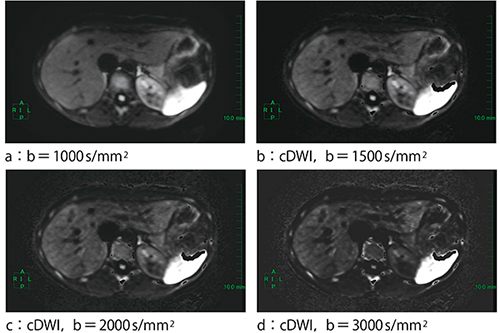

図2 実際のcDWIの画像

1.前立腺(図5)

前立腺は,b=1000s/mm2(図5 b)では不十分であり,b=2000s/mm2(図5 c,d)とすることで病変部がコントラスト良く明瞭に描出される。

また図5 dは,cDWIによるb=2000s/mm2の画像であるが,通常のb=2000s/mm2(図5 c)と比較しても遜色のない画像となっている。

図5 前立腺

2.膀 胱(図6)

骨盤内病変の検索中に偶然発見した膀胱がん例である。b=1000s/mm2(図6 a)では膀胱内の信号は完全に低下しておらず,病変とのコントラストが少し悪かったため,スライダーバーで画像を確認しながらb値の調整を行い,膀胱内の信号が低下するb値(図6 b)のcDWIを作成した。

このように後から作成できるのは,cDWIの強みである。

図6 膀胱